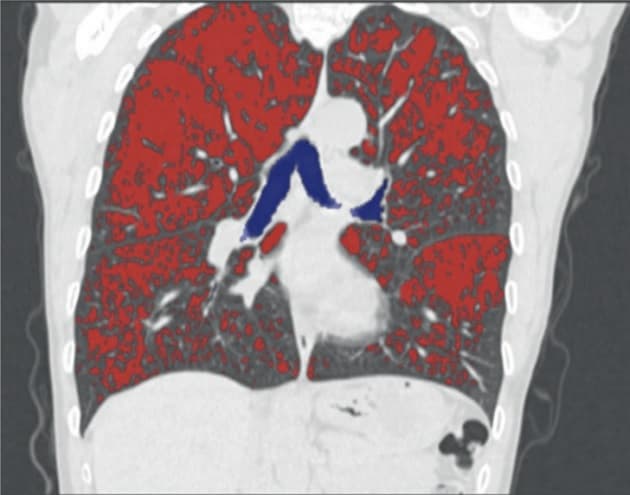

© Med CT-software visualiseres emfysemfordelingen i lungerne, markeret med rødt.

Svært emfysem med destruktion af alveolerne ses hos mange patienter med svær KOL. Forandringerne medfører pulmonal hyperinflation og kan give invaliderende åndenød. Ved lungevolumenreducerende kirurgi fjernes det ikkefunktionsdygtige lungevæv, hvilket er med til at genoprette brystkassens ventilatoriske funktion, reducere åndenød og forbedre overlevelsen. I statusartiklen beskriver Nodin et al udviklingen af de kirurgiske teknikker og de kriterier, som ligger til grund for udvælgelse af egnede patienter.